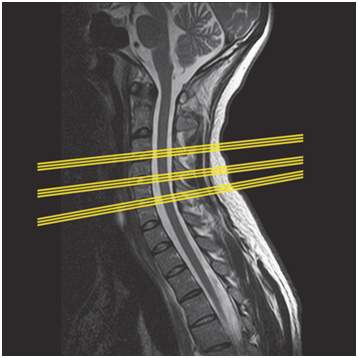

Ситуацию может усугубить еще один параметр исследования – расстояние между слайсами. Это реальное расстояние в мм между центрами слайсов по соответствующей оси. Если оно больше толщины слайсов, то образуются зазоры, информация из которых потеряна. Если меньше, то слайсы частично перекрывают друг друга. Потерянную информацию полностью восстановить невозможно, хотя существует множество способов 3D-реконструкции с интерполяцией промежуточных данных (например).